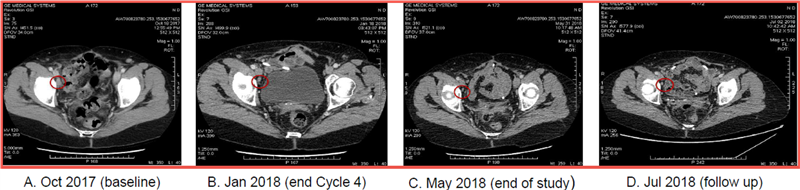

Exhibit 9 shows the progressive tumor reduction in the patient (subject 03-002) who went on to experience a partial response when treated with Cantrixil in combination with paclitaxel after completing Cantrixil monotherapy treatment.

This subject experienced substantial tumor shrinkage during the six-week period when she was treated with Cantrixil at 2.5mg/kg as a monotherapy. At the completion of Cantrixil monotherapy the patient subsequently received six cycles (18 weeks) of treatment with 2.5mg/kg Cantrixil combined with paclitaxel. The tumors continued to shrink and 12 weeks after entering the study the patient had achieved a partial response. The response was ongoing at the end of the 24-week follow-up period when the patient exited the study. Exhibit 9 also shows that the tumor shrinkage was maintained at a further assessment two months after the end of the study.

Exhibit 9: Progressive tumor reduction over an extended period observed in one patient